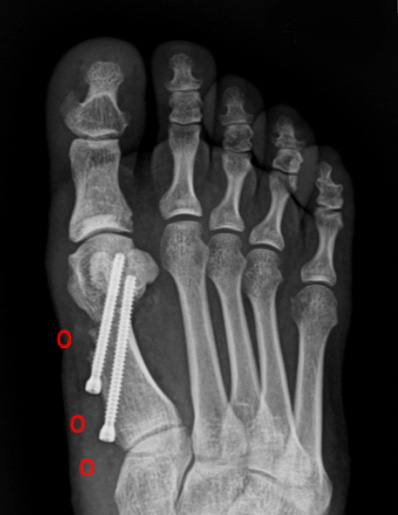

수술 전

수술 후

첫번째 사진을 보면 중족골두에서 근위지골의 기저부가 완전히 벗어나 있는 것을 확인할 수 있고,

수술 후에는 관절이 잘 맞아 들어간 것을 확인할 수 있습니다.